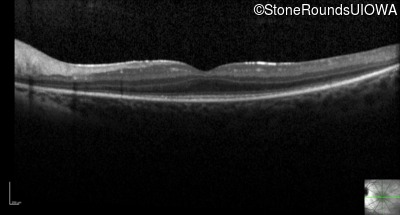

Optical Coherence Tomography - Right - 20/40

Exemplar / OCT Stack